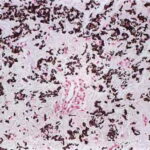

Histopathology. Histologic examination of the involved skin reveals considerable accumulations of swollen and irregularly clumped fibers staining like elastic fibers in the middle and lower thirds of the dermis; that is, they stain deeply black with orcein or Verhoetrs stain . Although normally elastic fibers do not stain with routine stains such as hematoxylin-eosin, the altered elastic fibers in pseudoxanthoma elasticum stain faintly basophilic because of their calcium imbibition. Staining for calcium with the von Kossa method also shows these fibers well. |

Histogenesis. Electron microscopic examination shows that the calcification occurs in normal-appearing elastic fibers . In some patients, especially in young persons, only some of the elastic fibers in the lower dermis are calcified, and the calcification is variable in degree. However, in adult patients, most elastic fibers show considerable calcification and, as a result, degeneration. Early calcification of elastic fibers consists either of diffuse granular deposits throughout the elastic fiber or of dense aggregates that may be located in the center or near the margin of the fiber (EM 5). With progression of the calcification, the elastic fibers ultimately become fully calcified, showing marked swelling and bizarre distortions. In addition, heavy calcium deposits may be seen in the ground substance adjacent to elastic fibers and free in the ground substance. The presence of calcified material outside of elastic fibers can be explained by the disintegration of completely calcified elastic fibers . |

Besides varying numbers of normal collagen fibrils, irregularly twisted collagen fibrils and granulofilamentous aggregates are present. It appears unlikely that the process of calcification begins in the granulofilamentous material, as maintained by some authors who regard this material as an abnormal precursor of elastic fibers . It is probable that this misinterpretation has resulted from the examination of advanced lesions containing disintegrated calcified elastic fibers within the granulofilamentous material . In favor of a primary location of the calcification within elastic fibers is the important observation that in decalcified sections of endocardial lesions, the internal structure of the calcified segments of elastic fibers is very similar to that of the adjacent noncalcified segments. |